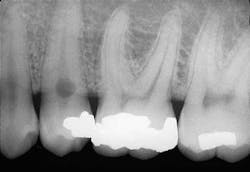

A 35-year old male visited a dental office for a routine checkup. Radiographic examination revealed a round radiolucency at the cervical region of tooth #29.

Based on the clinical examination of the patient, selected periapical radiographs, bitewings, and a panoramic film were ordered and exposed. A review of the films revealed a round radiolucency at the cervical area of the tooth #29 (see film). No other abnormalities were noted on the radiographs.

Internal resorption that occurs within the crown or the root of a tooth appears as a round or ovoid radiolucency. The outline of the internal resorption may appear smooth and well-defined, or ill-defined and scalloped. In some cases, the resorptive process may be so extensive that the entire crown or width of the root may be involved.